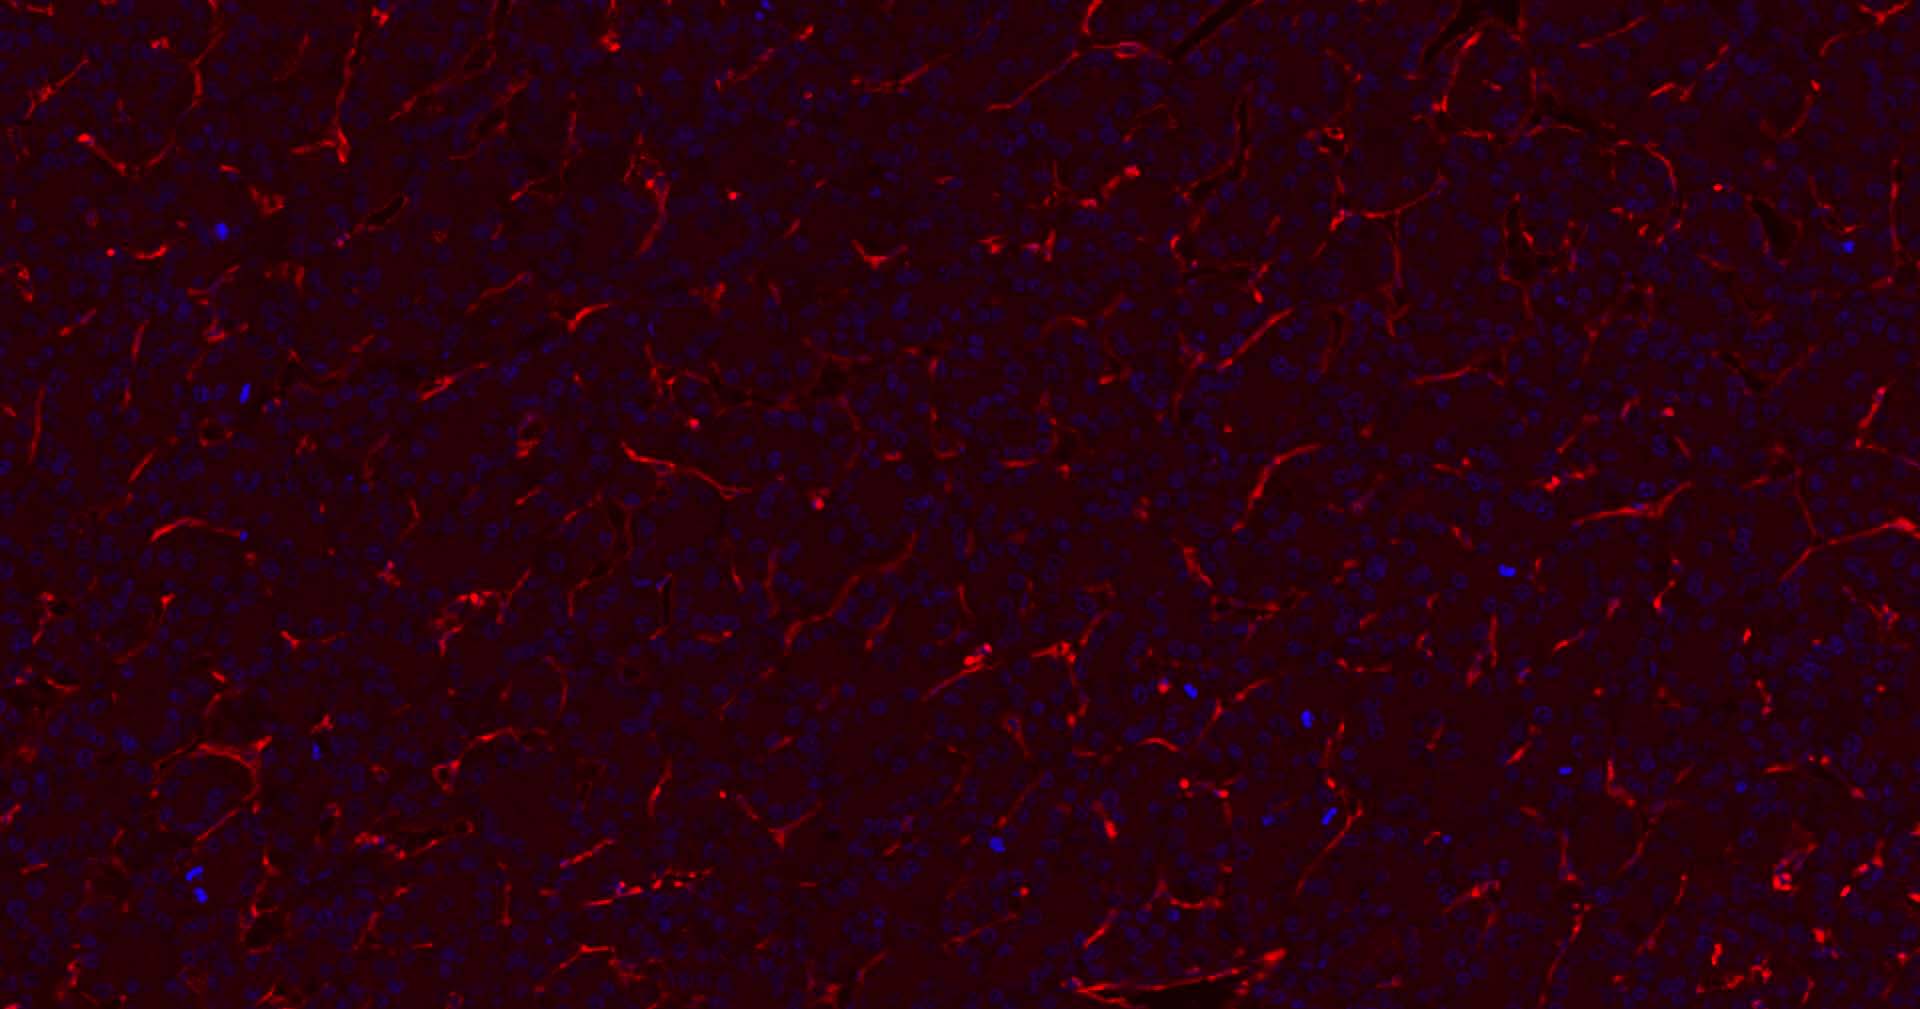

| IHC-P | Human | 1:200-2000 | |

| IHC-F | Human | 1:200-2000 | |

Expressed on platelets and leukocytes and is primarily concentrated at the borders between endothelial cells (PubMed:18388311, PubMed:21464369).

Cell adhesion molecule which is required for leukocyte transendothelial migration (TEM) under most inflammatory conditions (PubMed:19342684, PubMed:17580308).